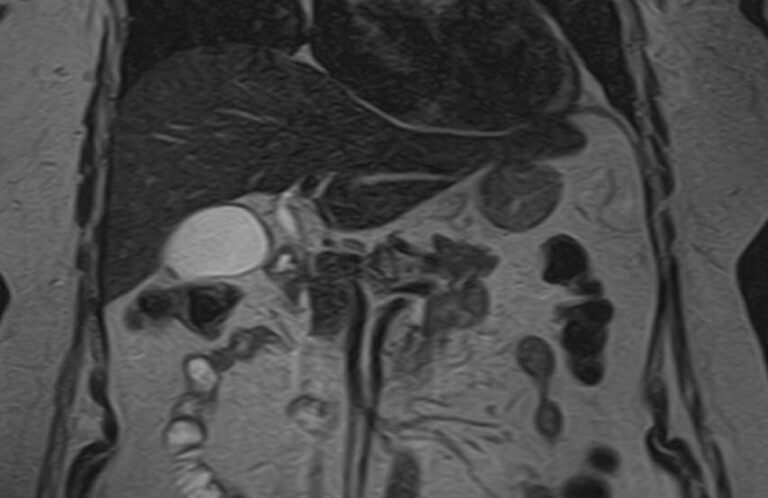

Магнитно-резонансная томография является современным наиболее информативным неинвазивным методом диагностики заболеваний печени. С помощью использования магнитного поля, обладающего высокой индукционной мощностью, МРТ позволяет получать послойные изображения органа и окружающих тканей и выявлять патологические изменения в печени на самых ранних стадиях развития, когда другие методы диагностики не дают результатов. Кроме того, процедура безболезненна и безопасна, так как организм не подвергается воздействию вредного рентгеновского излучения. Это позволяет назначать МРТ неоднократно в течение короткого промежутка времени, например, для оценки динамики состояния органа на фоне лечения.

В клинике «Доступная медицина» исследование проводится на современном высокопольном томографе экспертного класса TOSHIBA VANTAGE TITAN 1,5 Тесла. Аппарат послойно сканирует исследуемую зону в трех плоскостях с шагом от 1 мм, при этом получая данные о структуре органа в мельчайших подробностях. Инновационные компьютерные программы реконструируют данные в трехмерные модели органа, отображающие состояние не только паренхимы печени, но и внутрипеченочных желчных протоков и сосудистой системы.

Использование в процедуре МР-сканирования контрастирующих красителей позволяет выявить и охарактеризовать поражения печени размером от 1 мм, отличать доброкачественные и злокачественные новообразования, метастазы.

На томографических снимках хорошо заметны:

- доброкачественные очаговые поражения печени (гемангиома, очаговая узловая гиперплазия, гепатоцеллюлярная аденома, кисты (в том числе и паразитарные), липома, абсцесс, инфекции);

- злокачественные очаговые поражения печени;

- заболевания желчных протоков и желчного пузыря;

- диффузные болезни печени (стеатоз, воспалительные заболевания (вирусный гепатит, склерозирующий холангит), цирроз;

- патологии сосудов (тромбозы, артерио-венозные мальформации)

- рубцовые изменения после травм или операций